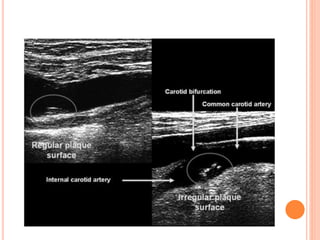

1-INFORMATION ABOUT PLAQUE COMPOSITION AND

SURFACE

 Cervical duplex ultrasonography can directly visualize

atherosclerotic plaque composition that can be classified

based on its echogenicity.

 Uniformly hyperechoic carotid plaques are mainly

composed of fibrotic tissue needed for plaque stability.

 In contrast, heterogeneous (and predominantly

hypoechoic) plaques consisting of matrix deposition,

cholesterol accumulation, necrosis, calcification, and

intraplaque hemorrhage are considered unstable, being

the source of artery-to-artery embolic strokes

1-INFORMATION ABOUT PLAQUECOMPOSITION AND SURFACE  Cervical duplex ultrasonography can directly visualize atherosclerotic plaque composition that can be classified based on its echogenicity.  Uniformly hyperechoic carotid plaques are mainly composed of fibrotic tissue needed for plaque stability.  In contrast, heterogeneous (and predominantly hypoechoic) plaques consisting of matrix deposition, cholesterol accumulation, necrosis, calcification, and intraplaque hemorrhage are considered unstable, being the source of artery-to-artery embolic strokes